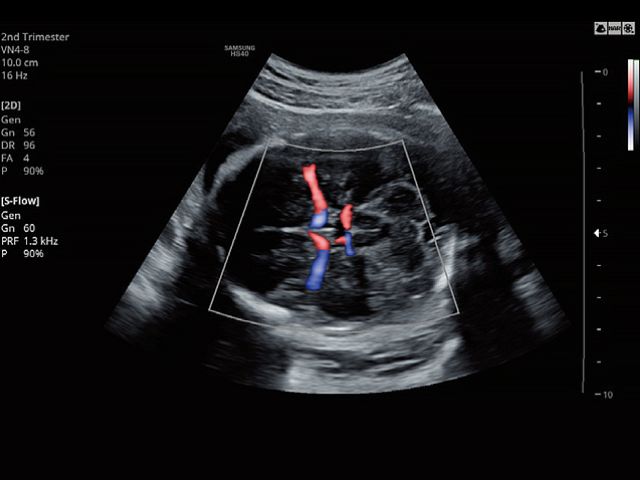

VN4-8Application:Abdomen, Obstetrics, Gynecology, Musculoskeletal, Pediatric, Vascular, Urology |